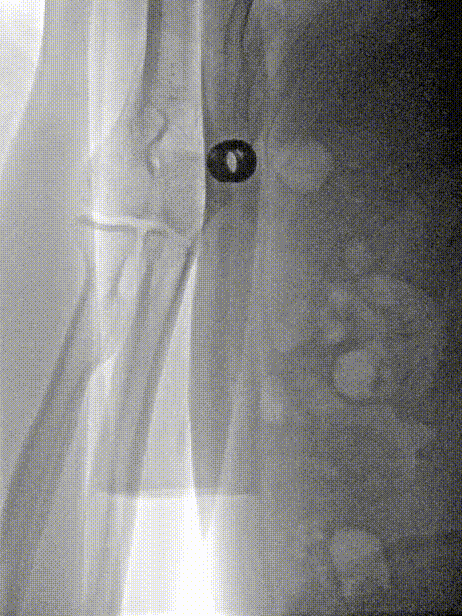

右侧桡动脉穿刺建立入路,交换技术直接经260cm泥鳅导丝置入6F 115cm 中间导管。

经6F中间导管,微导丝到位后引导Fastunnel®输送型球囊扩张导管到位至左侧大脑中动脉狭窄部位。

Fastunnel®输送型球囊扩张导管打压成形扩张狭窄病变部位,压力8atm,随后造影可见成形满意。